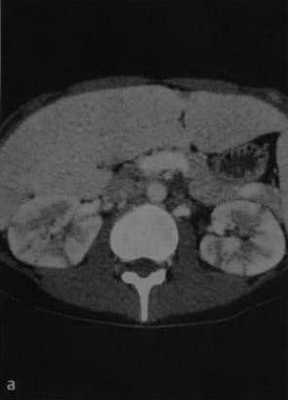

а, b Острый диффузный двусторонний пиелонефрит. Аксиальная (а) и фронтальная (b) КТ в кортикальной фазе. Множественные сегментарные участки сниженной перфузии в виде полос в корковом веществе почек.

КТ в нефрографической фазе демонстрирует двустороннее увеличение почек с гетерогенным контрастным усилением

При визуализации картина при пиелонефрите или абсцессе почки схожа с картиной при опухоли, поэтому результаты анамнеза, осмотра и других клинических данных помогают радиологу в постановке правильного диагноза. В представленном случае визуализируются гиподенсные образования в обоих почках. Если диагноз базировать только, исходя из данных изображения, то напрашивается следующий дифференциальный ряд: пиелонефрит, лимфома или метастаз.

Данный пациент поступил с жалобами на боль в боку и с анамнезом воспалительного поражения мочевыводящих путей, также у пациента отрицательный онкологический анамнез, поэтому диагноз — пиелонефрит.

На КТ спустя 4 месяца визуализируются нормальные почки. На первом изображении патологическая картина обусловлена мультифокальным пиелонефритом.